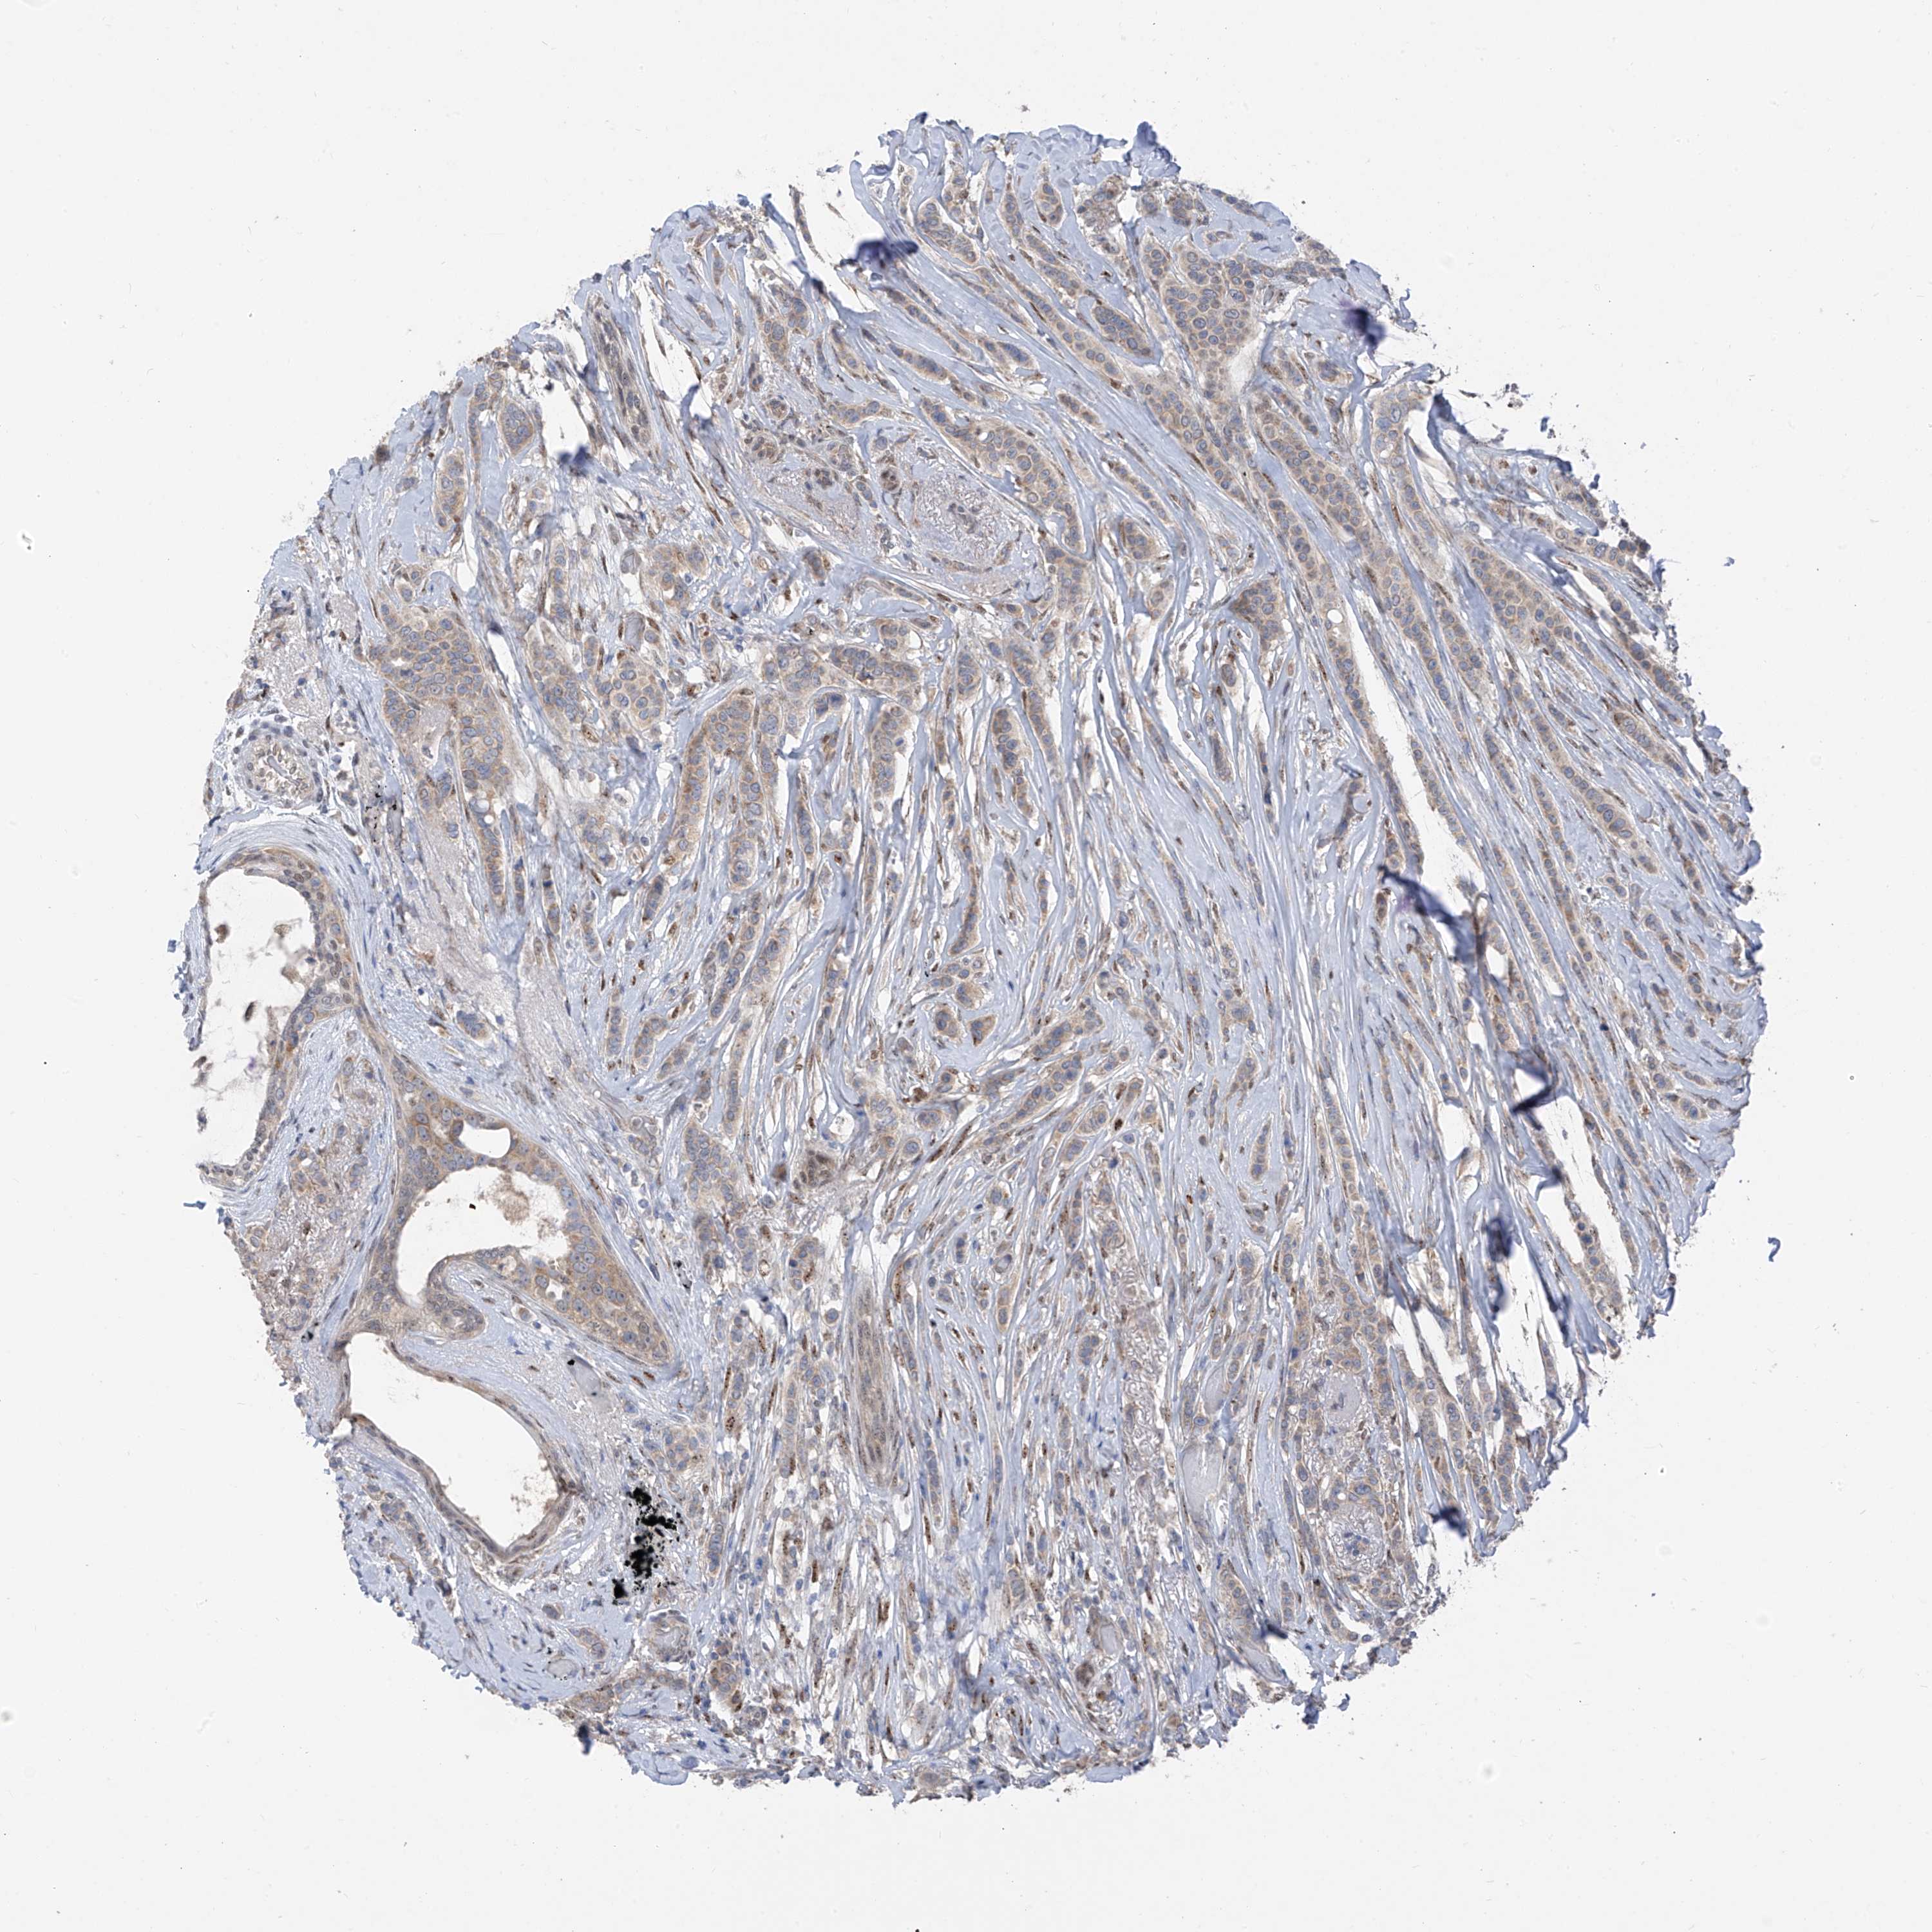

CANCER BREAST CANCER Show tissue menu

BRCA TCGA BRCA VALIDATION PROTEIN EXPRESSION

Breast cancer

Human cancer